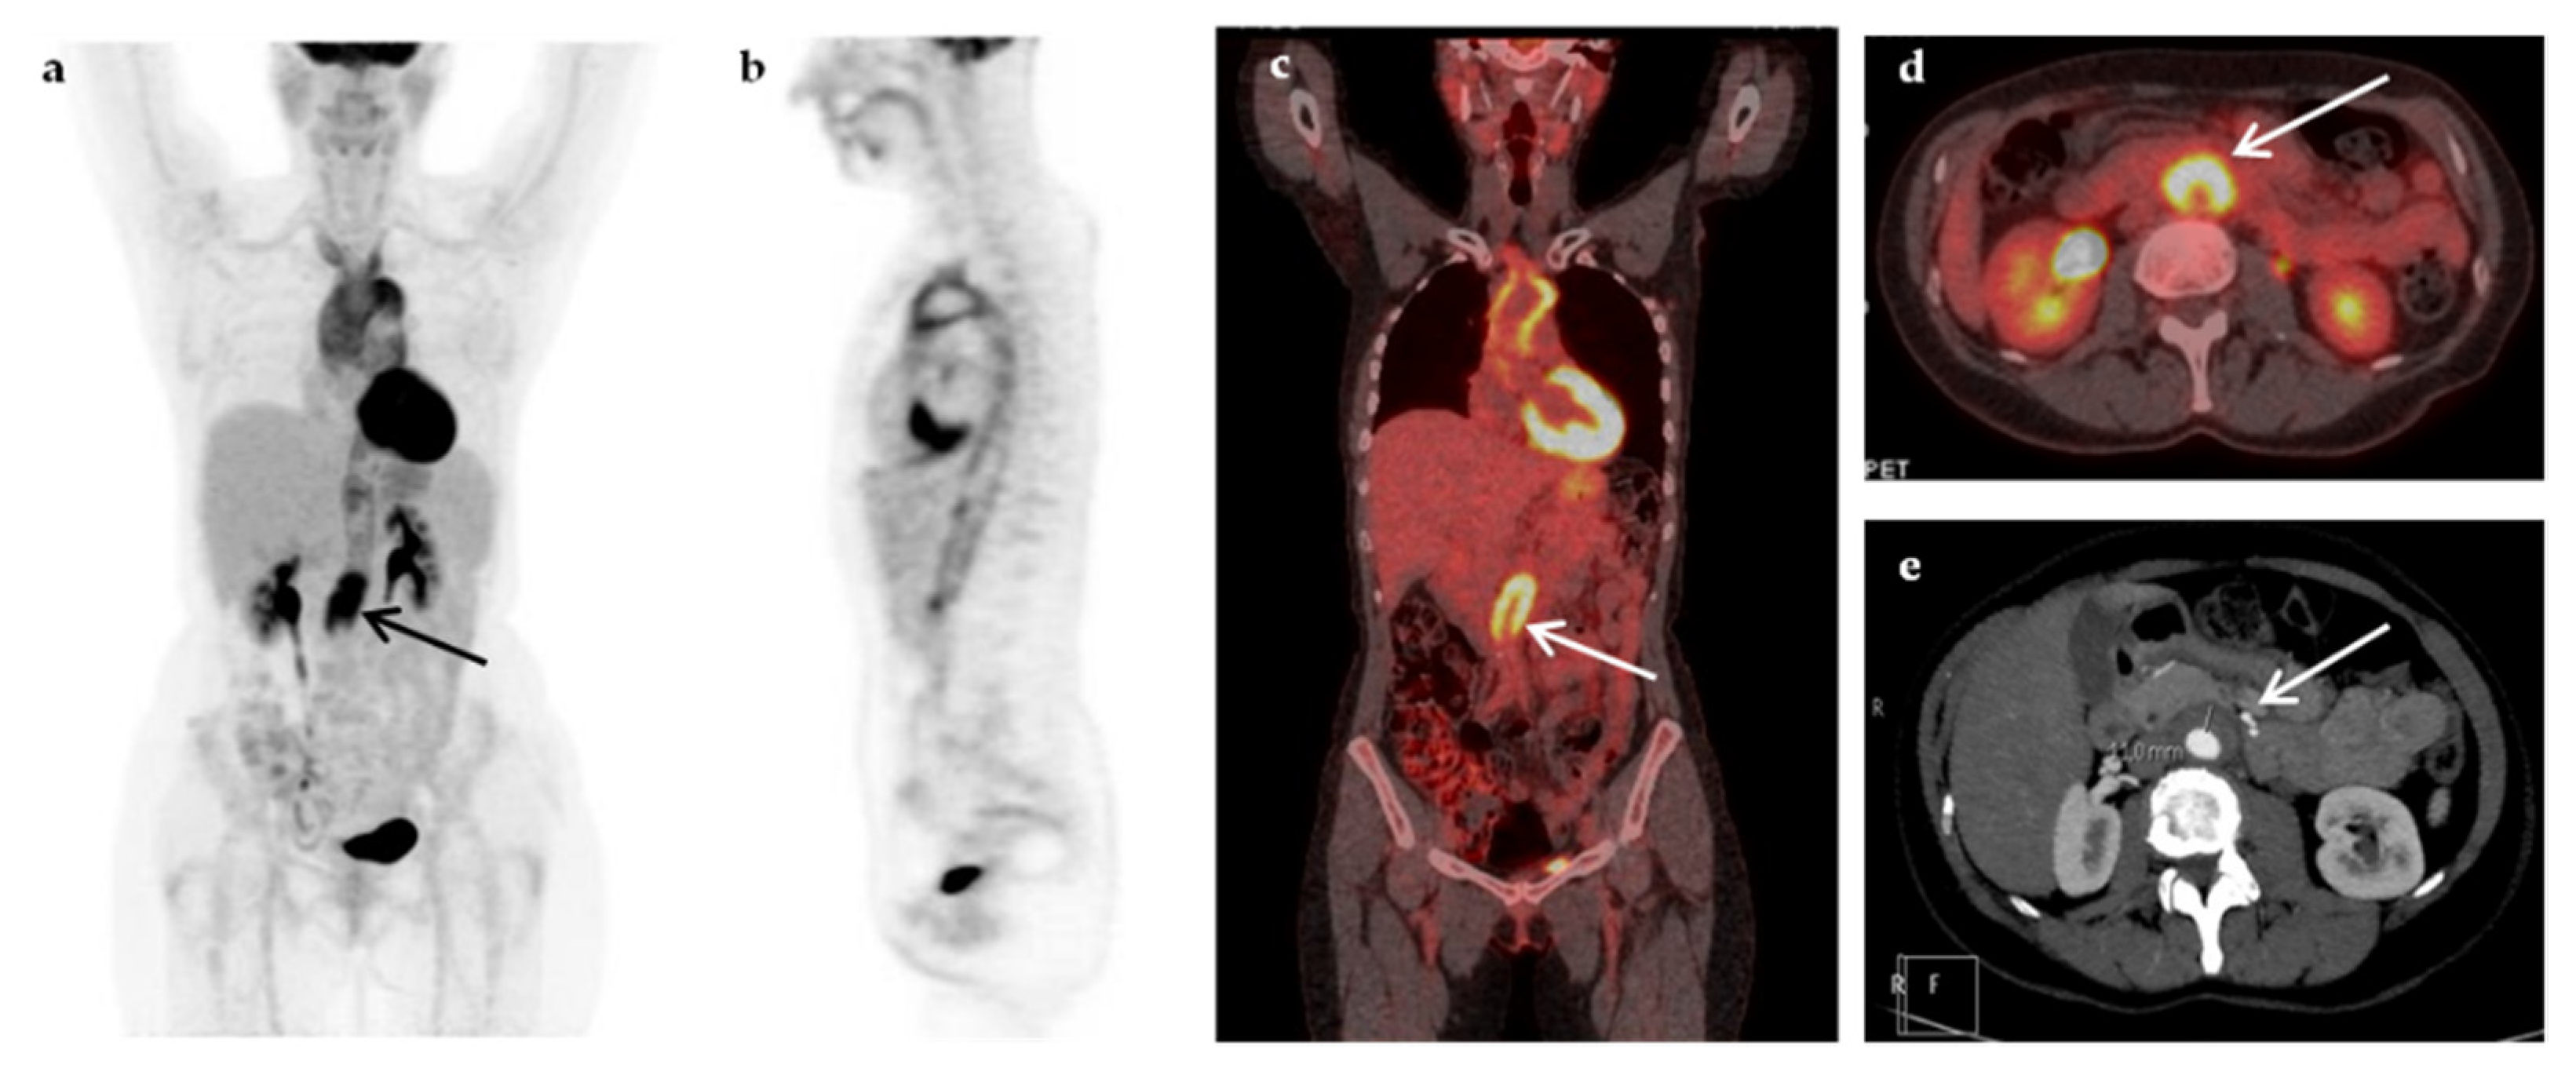

| Abdominal abscesses | 4 |

| Infectious cyst in polycystic renal disease | 3 |

| Vascular graft infection | 3 |